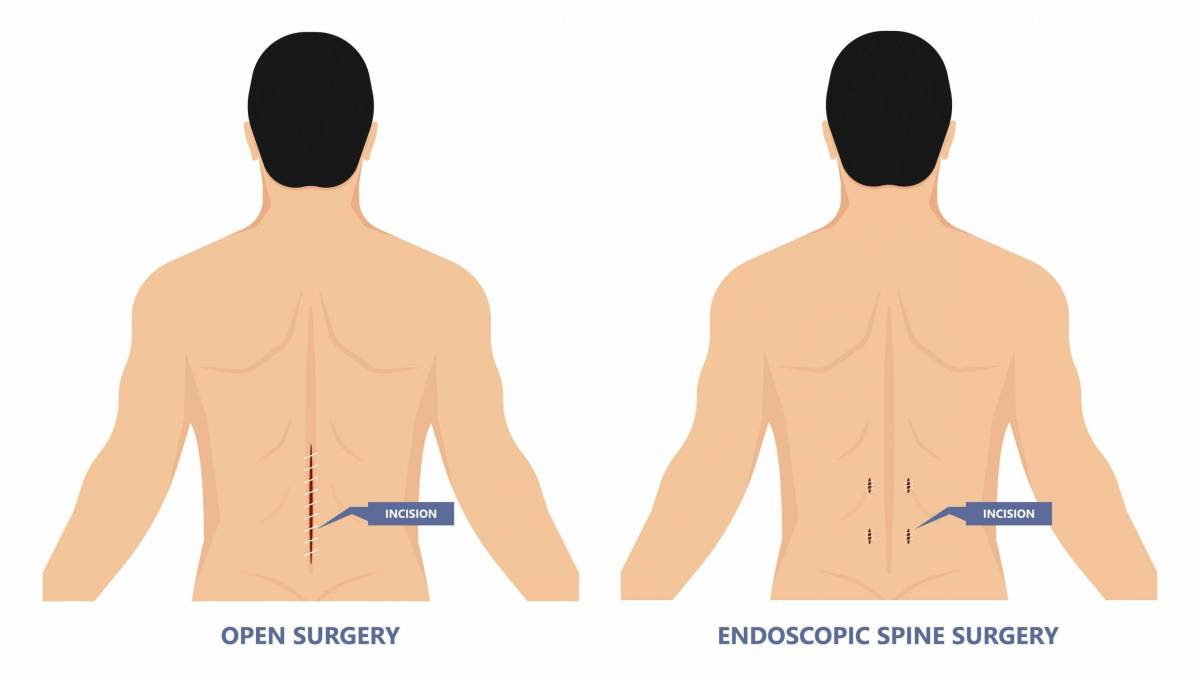

A Conservative(non-surgical) treatment is tried initially for most patients as most of our patients improve with the same. Surgery is offered when absolutely indicated and proven to give better results and are done with latest technologies at some of the best hospitals in Mumbai with well- equipped operation theatres.

Comparing Endoscopic Spine Surgery to Traditional Open Surgery: Which Is Right for You?

Recovery After Endoscopic Spine Surgery: What to Expect and How to Prepare

Understanding Endoscopic Spine Surgery: A Minimally Invasive Solution for Back Pain